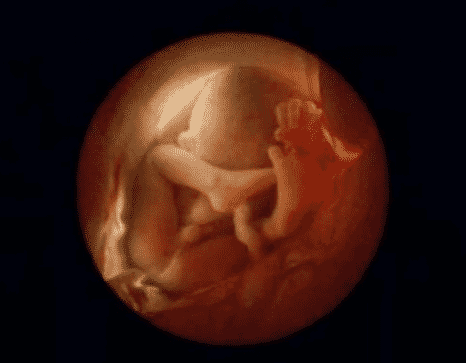

12. 8 semaines de développement